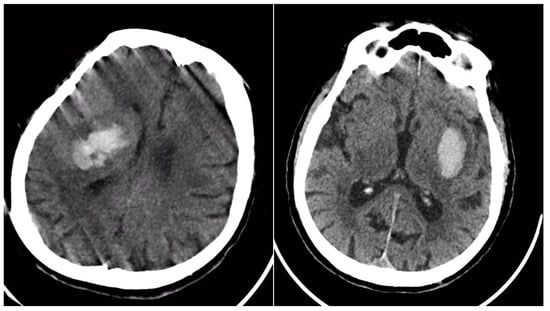

Table 3 presents the hematoma expansion status (YES = 89, NO = 315; total = 404) versus each baseline NCCT sign; column totals exceed 404 because any given patient could display more than one marker. All four signs were markedly over-represented in the expansion group: Blend Sign 28.1% vs. 11.4%, Black Hole Sign 56.2% vs. 23.8%, Irregular Shape 75.3% vs. 54.9%, and Satellite Sign 50.6% vs. 29.8% (all p < 0.001). The strongest association was for the Black Hole Sign, underscoring that discrete intra-hemorrhagic hypodensity denotes active or recurrent bleeding and substantially elevates the risk of volume growth (Figure 6).

Figure 6. (Left) ICH with expansion with the presence of BHS and IRS; (right) ICH without hematoma expansion; no NCCT signs observed.